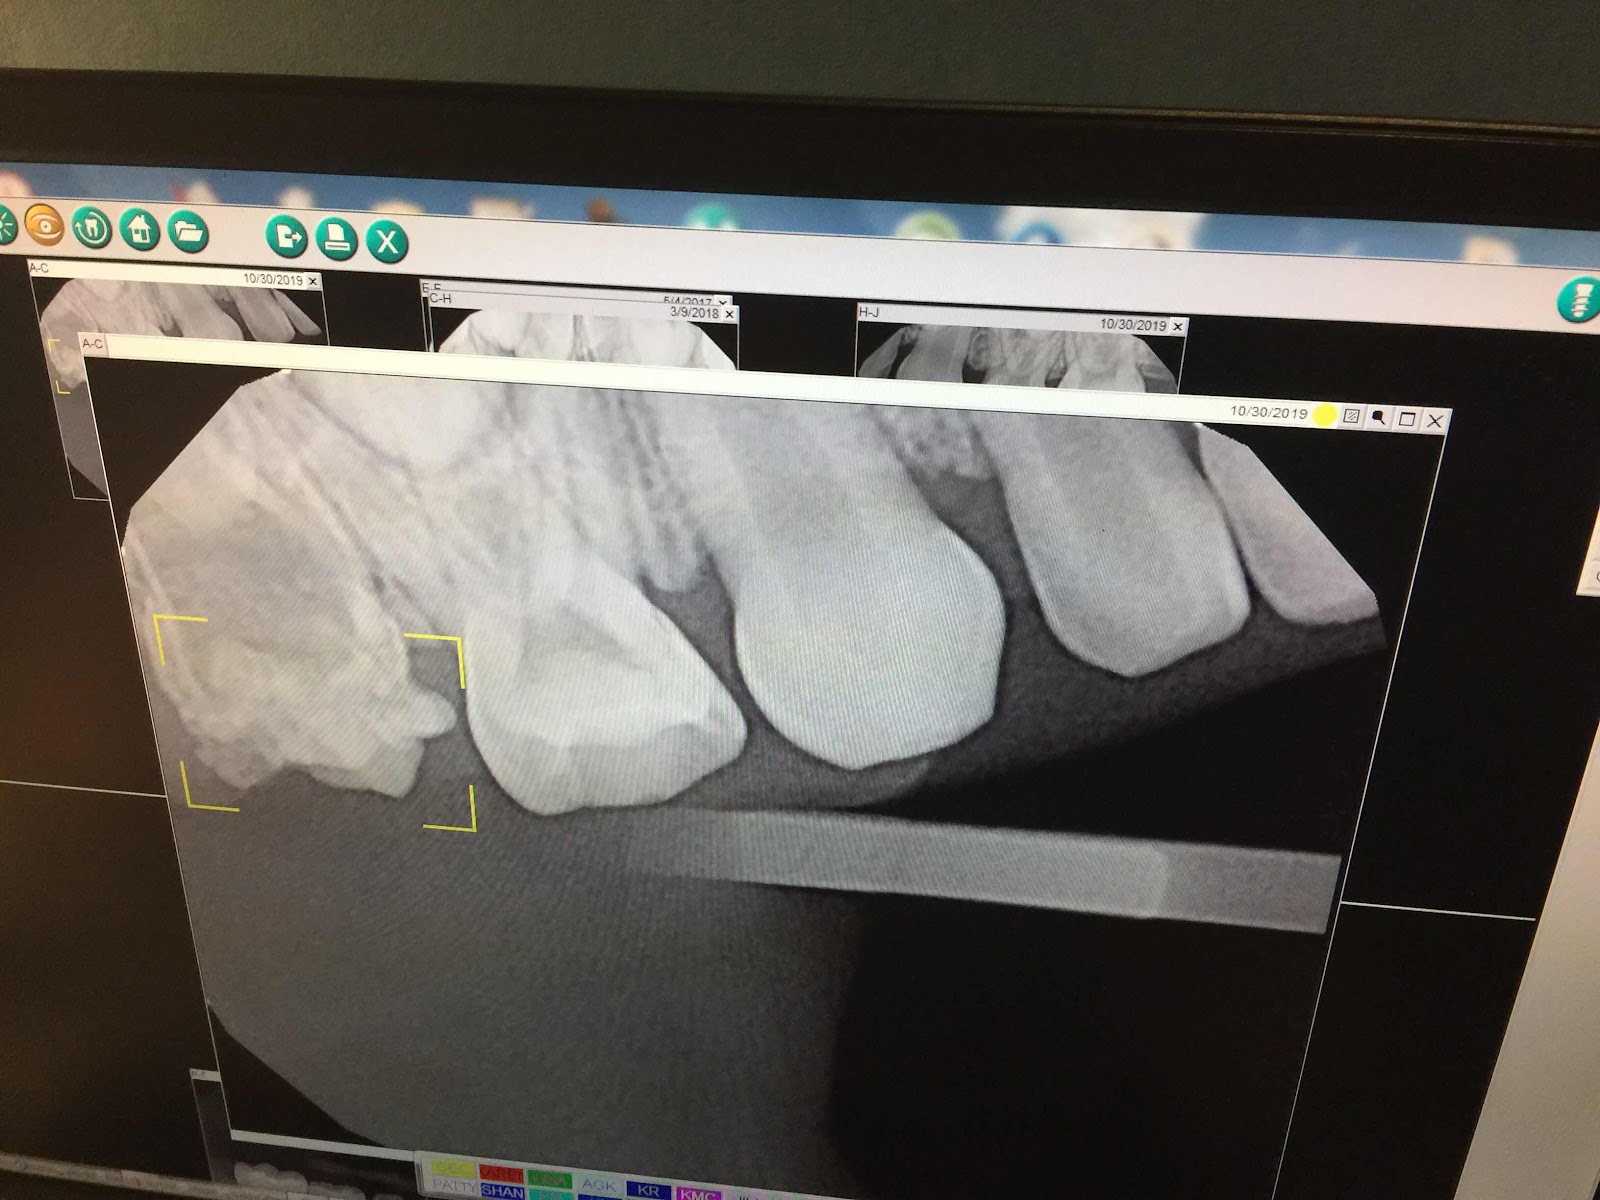

Dino tooth! Oh boy